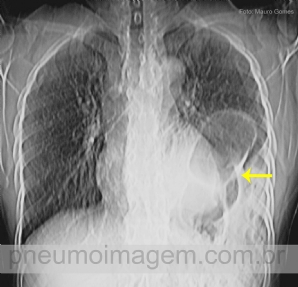

CASO CLÍNICO #42

A imagem não está tão nítida pois foi extraída de um corte de tomografia, mas o caso é bem interessante. O que a seta aponta nesse corte? Deixe os seus comentários abaixo! ***** The image is not so clear because it was extracted from a CT scan, but the c...